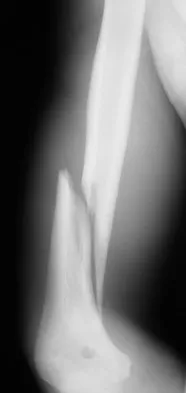

Question 50

A 35-year-old man sustained the closed injury shown in Figure 52 in his dominant extremity. Neurologic function is normal. Treatment should consist of

Explanation